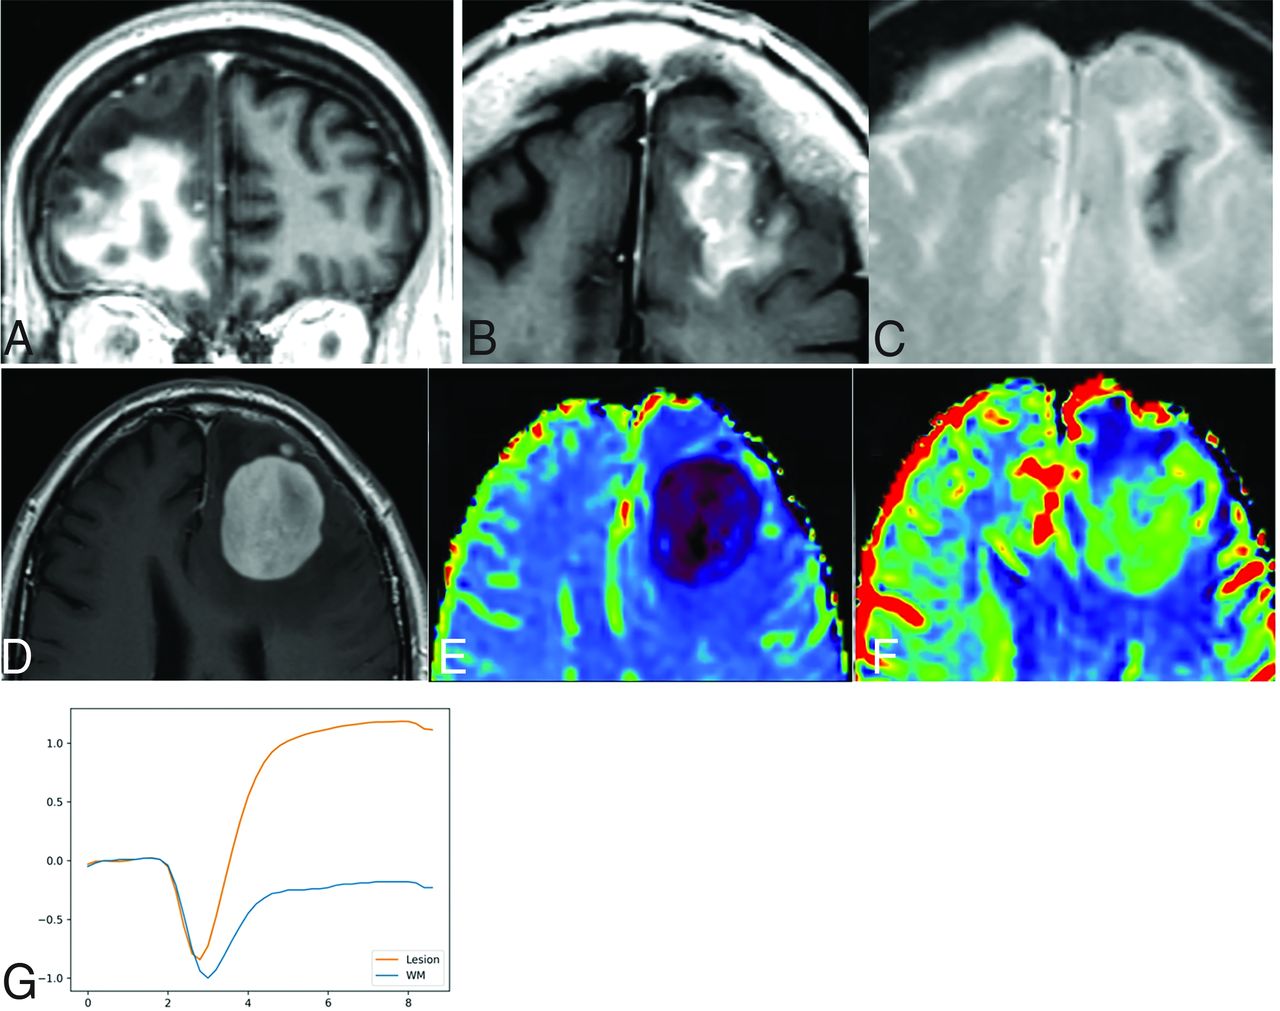

The CNS WHO classification 2021 includes low-grade B-cell lymphoma of the CNS, ALK+/ALK−, T-Cell, and NK/T-cell lymphoma classified as miscellaneous, rare lymphomas in the CNS.2 They represent a heterogeneous group of tumors with scarce evidence of concrete imaging findings. While low-grade B-cell lymphomas may occasionally appear as lymphoma-like lesions, other very different radiologic appearances are described, such as resembling edema, glial tumor, meningioma, and gliosis.41 Regarding anaplastic large-cell and T-cell or NK/T-cell lymphomas, some authors postulate that they may resemble lymphoma or lymphomatosis cerebri on imaging, with other nonspecific presentations also possible (Fig 7). In summary, very heterogeneous imaging presentations, occasionally resembling lymphoma, can be seen in this heterogeneous group of exceptional entities.41⇓-43

NK/T-cell lymphoma presenting with a lymphomatosis cerebri radiologic pattern (A–C). Patched and diffuse, bilateral and asymmetric, deep and subcortical, hyperintense lesions on FLAIR (A and B) without contrast enhancement (C).

Lymphomatosis cerebri corresponds to a clinical-radiologic pattern that is not included as a concrete histopathologic WHO entity. It may be observed in the context of different histologic lymphoma subtypes, but in most cases, it corresponds to primary DLBCL of the CNS. The typical clinical presentation is a subacute onset of dementia, cognitive impairment, and personality changes.44,45

It consists of a nonenhancing or scarcely-enhancing (30%) T2-FLAIR hyperintense infiltration of brain tissue. It is usually located in white matter regions, with different distributions ranging from focal to patched or diffuse. The main differential includes gliomatosis cerebri (also considered a radiologic pattern and not a WHO entity) and inflammatory and toxic-metabolic diseases. Of note, in this form of CNS lymphoma, brain lesions may be highly variable and change between near-in-time follow-up scans.44⇓⇓-47

In line with what was detailed in the intravascular lymphoma section, the detection of a tumoral pattern on 1H-MR spectroscopy without relevant amount of mIns (potential glial marker present in gliomatosis) in abnormal areas of T2-FLAIR hyperintensity, as well as the above-described characteristic DSC-PWI pattern in the possible enhancing lesions, supports presurgical suspicion46,47 (Fig 5).